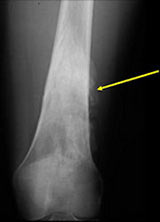

- There may be invasion of the medullary canal with long standing disease

MRI/CT:

- Useful for determining medullary invasion

- Can help discern areas that may be high grade